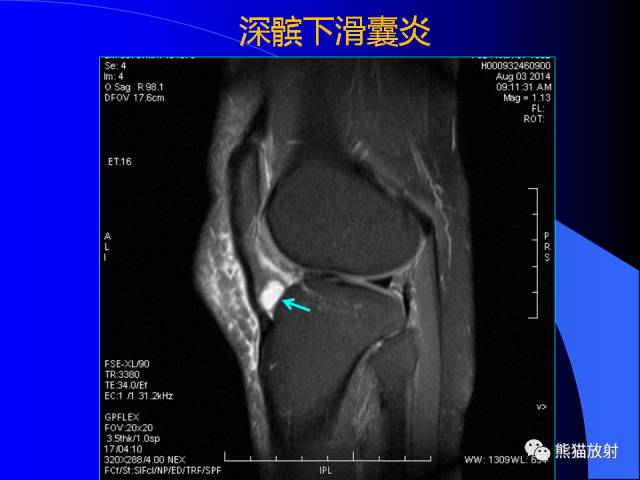

膝关节周围囊肿是较常见的病变,可以是原发的,多见于青年及儿童,囊内容物通常是黏液;也可以是继发的,多与关节腔相通,内含一般黏性的滑液,常继发于膝关节骨关节炎、类风湿关节炎、非特异性滑膜炎、半月板损伤、髌骨软骨软化症等。

以上滑囊出现炎症时均可形成滑囊囊肿。